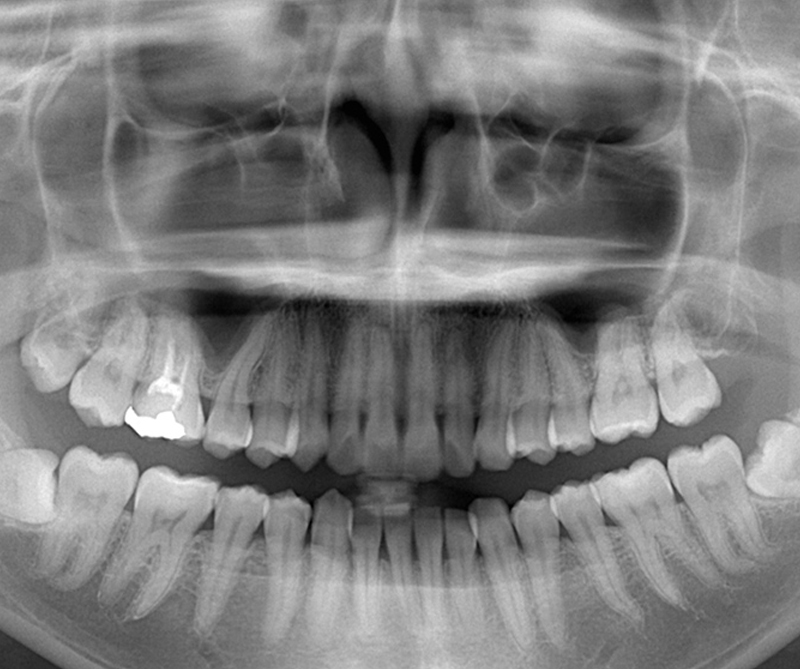

難しい親知らずの抜歯も対応

当院では、大学病院や総合病院であらゆる「難しい親知らず抜歯」を経験している歯科医師、日本口腔外科学会認定医の『外科処置のエキスパート』が親知らずの抜歯を行います。